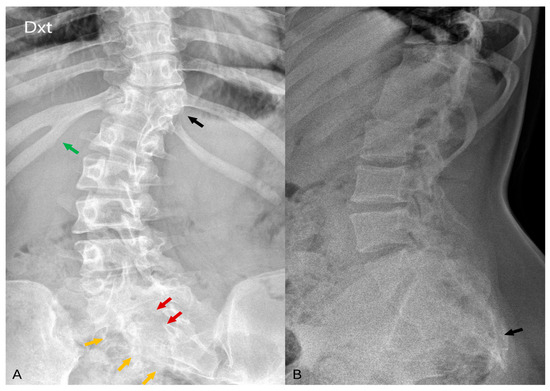

Figure 4.

(A,B) In the axial plane, T2 TSE imaging reveals diastematomyelia across multiple levels (green arrows), along with evident defects in the vertebral posterior arch (red arrows).